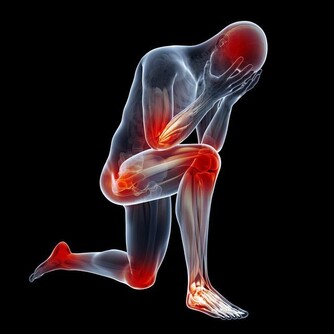

熱痙攣

通常發生在人進行劇烈運動目大量出時,人身體中的鹽分和水分隨汗液一同流失。肌肉中的含鹽量低可能是造成熱痙攣的原因。此外,停攣也可能是熱衰竭的一種表現。

1怎樣識別

表現為肌肉或抽描,發生在腰部手臂或部。常呈對稱性,時而發作。患者意識醒,體溫一般正常。

2怎樣處理

停止一切活動,靜坐在涼爽的地方休息;飲用稀釋、清爽的果汁或運動飲料;痙攣緩解後的幾小時內勿進行重體力勞動劇運動;如果病人有心髒病史、低鹽飲、小時後熱的狀況還沒有消退,要尋求專業的醫療處理。